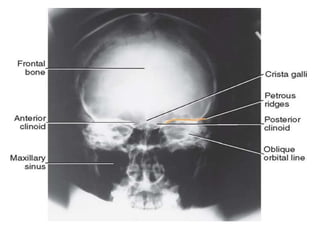

CRANIUM.

Occipito-Frontal (OF).

• The patient faces the skull table/x ray couch, with

forehead resting against it.

• The base line and median sagittal plane must be at right

angles to the film.

• Appropriately marked 24 x 30 cm cassette is

longitudinally placed.

• Centre; To the glabella, with tube angled either;

5°Caudad to show petrous bones within the orbits. Or

20°Caudad to project the petrous bones below the level

of the orbits.